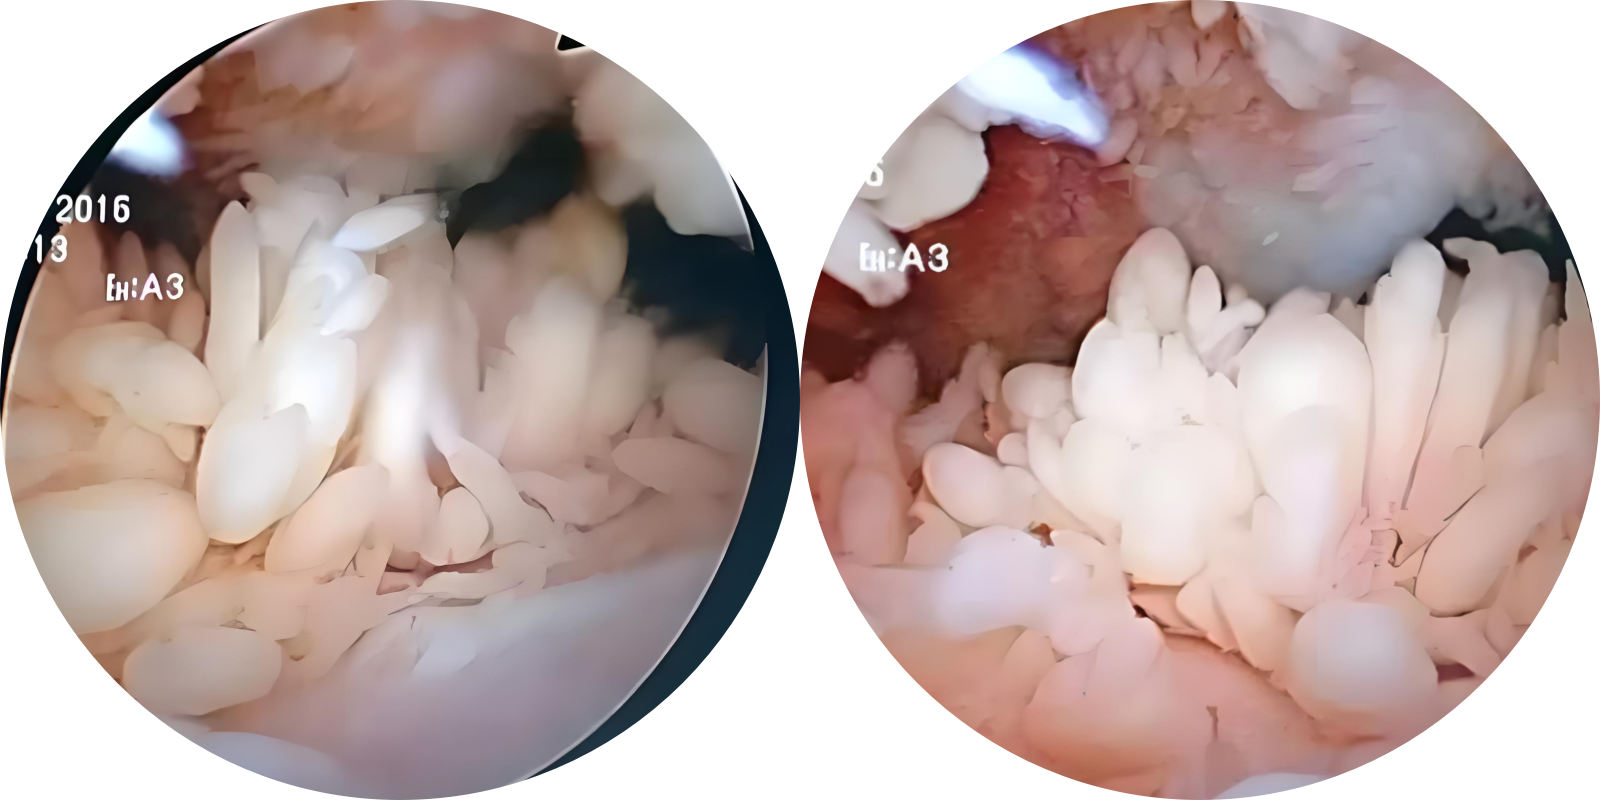

关节镜下肉眼观:滑膜多发粗大乳头状、绒毛状凸起,呈浅黄色,表面覆盖有半透明滑膜组织。

镜下观:滑膜呈绒毛状增生,滑膜下层见大量脂肪细胞浸润以及扩张毛细血管。部分病例有不同程度淋巴细胞、浆细胞浸润。